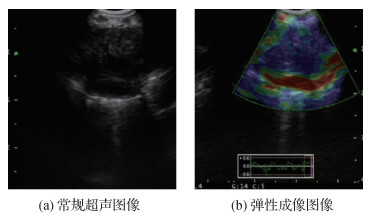

• U-Net支气管超声弹性图像纵膈淋巴结分割

U-Net支气管超声弹性图像纵膈淋巴结分割

摘要:目的超声弹性成像技术已逐步应用于支气管淋巴结良恶性的诊断,帮助确定肺癌分期。在支气管超声弹性图像中,淋巴结区域的精确定位对诊断准确度具有重要影响,但通常依赖专业医师的手动分割,费时费力。为此,本文设计了一种注意力上下文编码器网络(attention context encoder network,ACE-Net)。方法本文网络模型包括编码器、上下文提取器和解码器3部分。使用在ImageNet数据集上预训练且去掉平均池化层和全连接层的34层残差网络ResNet-34作为编码器提取特征,上下文提取器从编码器的输出中进一步提取高级语义信息,同时保留尽可能多的空间信息,基于AG(attention gate)的解码器可以抑制输入图像中的不相关区域,同时突出对当前任务更关键的特征。结果实验在本文收集的包含支气管超声弹性图像及对应分割标签的数据集上进行,与6种典型的U-Net结构深度网络模型的分割性能进行对比,数据集中的每幅图像中的淋巴结都由专业医师手动分割标注。基础U-Net网络得到淋巴结分割结果的Dice系数、敏感度和特异度分别为0.820 7、85.08%和96.82%,其他改进网络的分割性能在此基础上均有一定提高,本文方法的Dice系数、敏感度和特异度分别为0.845 1、87.92%和97.04%,Dice系数和敏感度在所有方法中取得了最优值,特异度取得了次优值。结论以U-Net为代表的深度学习模型在支气管超声弹性图像淋巴结分割问题中具有很大潜力,将上下文提取器和注意力机制融入U-Net网络可以一定程度提升分割精度。本文收集的数据集将有助于推动支气管超声弹性图像淋巴结分割问题的研究。

关键词:超声弹性成像;淋巴结分割;深度学习;U-Net;上下文提取器;注意力机制